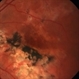

- serpiginous choroiditis

- Imaging device

- Fundus camera

- Serpiginous choroiditis, right eye #1. Advanced pigmented scar formation ( fovea involved).